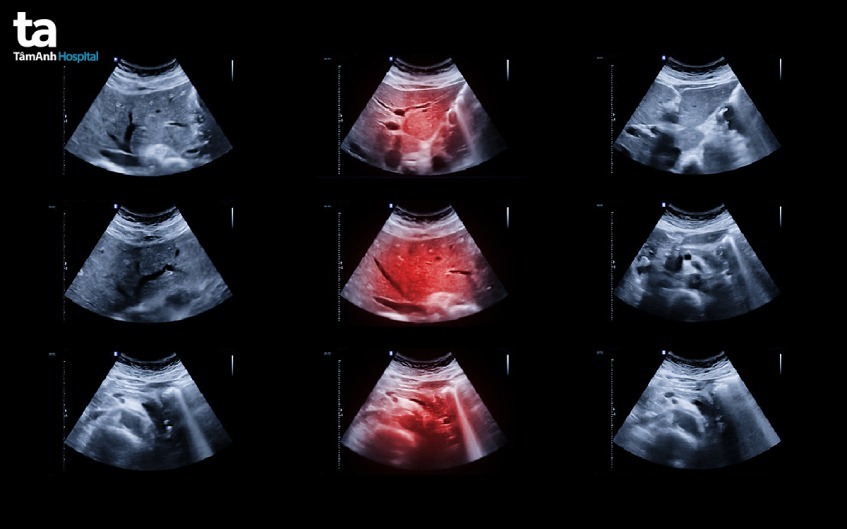

Đây là một trong những phòng khám chuyên khoa gan tại TPHCM được nhiều người bệnh tin tưởng lựa chọn. Tại đây quy tụ đội ngũ y bác sĩ chuyên khoa gan dồi dào kinh nghiệm. Song song đó, đơn vị còn tập trung đầu tư hệ thống máy móc hiện đại như máy nội soi Olympus EVIS X1 CV – 1500 được tích hợp trí tuệ nhân tạo (AI) hoặc Fuji 7000 hiện đại, máy siêu âm có đàn hồi mô Aixplorer Mach 30 Supersonic Imagine (Pháp), Hệ thống phẫu thuật nội soi 3D/4K ICG Rubina Karl Storz… Những thiết bị này hỗ trợ đắc lực cho bác sĩ trong chẩn đoán và điều trị bệnh, nâng cao hiệu quả và giảm tối đa biến chứng nghiêm trọng.

Phòng khám gan uy tín được trang bị đầy đủ hệ thống máy móc hiện đại. Không chỉ hỗ trợ công tác khám và chẩn đoán, hệ thống máy móc tối tân còn giúp bác sĩ thao tác dễ dàng trong quá trình phẫu thuật. Điều này vừa nâng cao hiệu quả điều trị, vừa đem lại trải nghiệm thăm khám và chữa bệnh tốt nhất cho bệnh nhân. Đặc biệt, việc ứng dụng công nghệ mới như trí tuệ nhân tạo (AI) vào chữa bệnh giúp tăng độ chính xác trong quá trình điều trị bệnh gan.

Chuyên khoa gan còn được trang bị hệ thống máy móc hiện đại chuyên dùng cho việc điều trị bệnh như máy sinh thiết gan, máy siêu âm, máy nội soi… Tất cả góp phần hỗ trợ bác sĩ chẩn đoán chính xác mức độ tổn thương, từ đó đưa ra phương pháp chữa trị tối ưu nhất. Đó chính là lý do vì sao nên khám ở chuyên khoa gan.